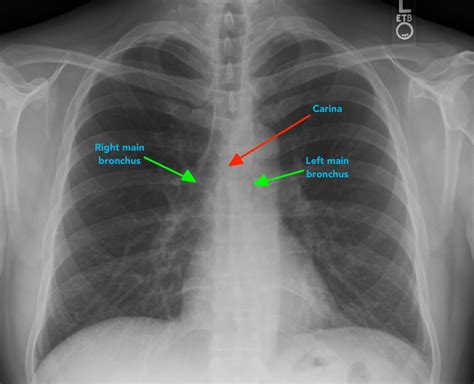

A normal lung X-ray typically shows clear lung fields with no signs of inflammation, infection, or other abnormalities. The lungs appear black due to the air they contain, while the heart and other structures appear white. The diaphragm, the muscle that separates the chest from the abdomen, is also visible and should be at a normal level.

Here are some key features of a normal lung X-ray:

• Clear lung fields with no opacities or infiltrates.

• Normal heart size and shape.

• Visible costophrenic angles (the angles where the ribs meet the diaphragm).

• No pleural effusions (fluid accumulation around the lungs).

• Normal vascular markings.